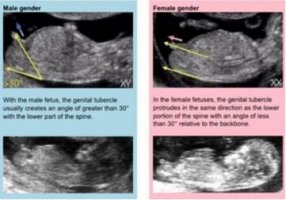

[生男生女]孕期准爸妈们听说过很多看男女的方法,除了常见的酸儿辣女和怀男孩肚子尖尖,怀女孩肚子圆圆等说法外,据说很多孕期产检项目也能看男女,比如NT检查。下面小编整理了关于NT检查看男女